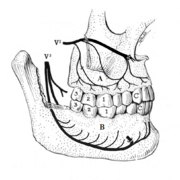

Pericoronitis

Pericoronitis is inflammation of the soft tissues surrounding the crown of a partially erupted tooth.[24] The lower wisdom tooth is the last tooth to erupt into the mouth, and is, therefore, more frequently impacted, or stuck, against the other teeth. This leaves the tooth partially erupted into the mouth, and there frequently is a flap of gum (an operculum), overlying the tooth. Bacteria and food debris accumulate beneath the operculum, which is an area that is difficult to keep clean because it is hidden and far back in the mouth. The opposing upper wisdom tooth also tends to have sharp cusps and over-erupt because it has no opposing tooth to bite into, and instead traumatizes the operculum further. Periodontitis and dental caries may develop on either the third or second molars, and chronic inflammation develops in the soft tissues. Chronic pericoronitis may not cause any pain, but an acute pericoronitis episode is often associated with pericoronal abscess formation. Typical signs and symptoms of a pericoronal abscess include severe, throbbing pain, which may radiate to adjacent areas in the head and neck,[20][25]:122 redness, swelling and tenderness of the gum over the tooth.[26]:220–222 There may be trismus (difficulty opening the mouth),[26]:220–222 facial swelling, and rubor (flushing) of the cheek that overlies the angle of the jaw.[20][25]:122 Persons typically develop pericoronitis in their late teens and early 20s,[27]:6 as this is the age that the wisdom teeth are erupting. Treatment for acute conditions includes cleaning the area under the operculum with an antiseptic solution, painkillers, and antibiotics if indicated. After the acute episode has been controlled, the definitive treatment is usually by tooth extraction or, less commonly, the soft tissue is removed (operculectomy). If the tooth is kept, good oral hygiene is required to keep the area free of debris to prevent recurrence of the infection.[20]:440–441